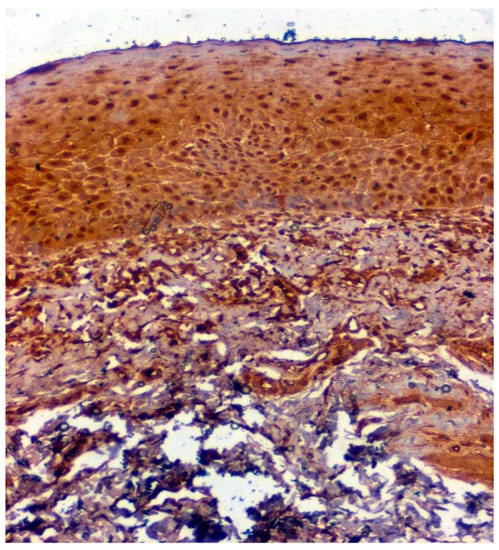

Figure 5.

IHC of CA 1 in OSMF samples (under 20× magnification).

Positive immunoexpression for CA 1 was found in 70.4% (88/125). Among the 40 patients with OSCC, CA 1 overexpression was found in 75% (30/40), and among the OSMF patients, CA 1 overexpression was found in 77.8% (56/72) compared to 15.4% (2/13) of normal, which was found to be statistically significant (p = 0.000; χ2 = 21.169) (Table 3). Based on different degrees of epithelial abnormalities, we found a statistically significant association (p = 0.025; χ2 = 11.144). Our results showed epithelial atrophy among the OSMF patients showing positive CA 1 overexpression. There was no significant association between CA 1 expression and degrees of inflammation, fibrosis and vascularity. Figure 4 shows the negative immunoexpression of CA1 in normal samples. Figure 5 shows the CA 1-positive immunoexpression in epithelial cells in OSMF samples, with cytoplasmic and nuclear positivity. In OSCC samples, CA 1 demonstrates strong cytoplasmic and nuclear positivity in malignant epithelial cells (Figure 6).